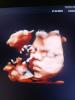

Просто класс фото.

А какой у Вас тут примерно срок на 3 д снимки

@elena2024luz за 2 месяца до родов